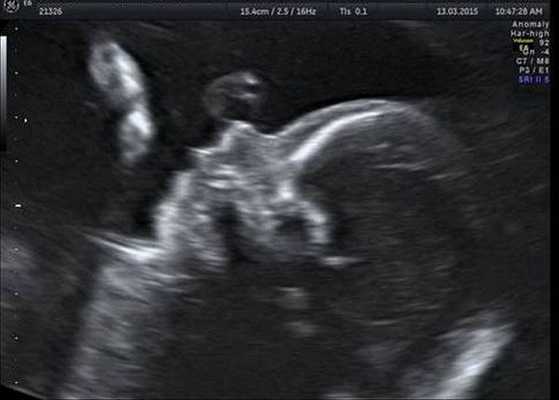

Врожденные аномалии лица в основном определяются еще в антенатальном периоде при плановом УЗ-скрининге беременной. При этом врач оценивает размеры и глубину поражения, чтобы заранее спланировать ход реконструктивной операции, скорректировать протокол ведения родов. При подозрении на сочетанные нарушения проводится амниоцентез, кордоцентез с последующей генетической диагностикой. В постнатальном периоде назначается полный комплекс обследований:

Генетический сбой в период закладки челюстно-лицевой системы приводит к развитию дефектов - незаращению верхней губы и неба. Распознать наличие волчьей пасти у плода возможно по УЗИ лишь на поздних сроках беременности. Дети с заячьей губой и волчьей пастью болезненны, т. к. вдыхаемый ими воздух не согревается и не увлажняется, что приводит к развитию воспалительных процессов дыхательных путей и внутреннего уха. У таких пациентов отмечаются изменения челюстно-лицевого скелета, зубочелюстного ряда, слухового аппарата. Незаращение нёба и верхней губы может встречаться изолированно или сочетаться вместе и с другой челюстной патологией.

По шкале влияния на формирование заячьей губы неблагоприятные факторы располагаются в следующей последовательности: химические (22,8%), психические (9%) механические травмы (6%), биологические (5%), физические (2%) и т. д. Определить рождение ребенка с заячьей губой можно по данным ультразвукового исследования плода на поздних этапах беременности. Родителям, уже имеющим ребенка с расщелиной губы, перед планированием следующей беременности показано медико-генетическое консультирование.